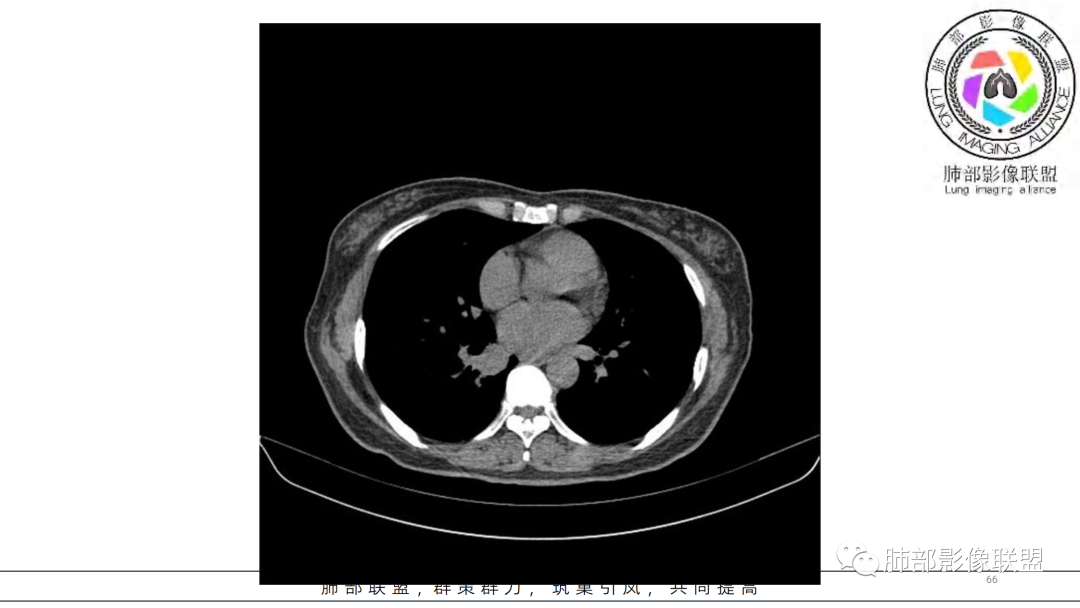

2.右肺下叶及中间段支气管后方类圆形块影,边界较清楚,未见分叶及毛刺,病灶部分突入支气管腔内(冰山一角),局部管腔狭窄,相应肺叶未见片影或体积变化。

3.块影密度均匀,未见液化坏死及钙化,渐进性强化,强化显著。

中青年女性,支气管管腔内外肿块(“冰山征”),边界较清楚,强化显著,未见阻塞性肺不张,尽管未出现“类癌综合征”临床表现,仍然符合典型类癌影像学表现。

类癌临床表现无特异性,影像学检查仍然是肺类癌的主要诊断依据。其特征性表现是孤立的、边界清楚的肿物,密度可均匀或不均匀,边缘多清楚锐利,部分病例可见浅分叶及毛刺。类癌侵及的支气管局部增厚,与正常的管壁分界清楚,局部呈乳头状突起,表面光滑。肺门旁肿块往往边缘光整、轮廓清楚、密度均匀,增强扫描大多呈均匀明显强化,可有持续强化或延迟强化。中央型肺类癌可引起支气管壁局限性增厚,形成轮廓光滑的管壁结节,并与腔外大病灶形成“冰山征”。少数病例可沿支气管腔内长轴生长,呈指套样改变,类似肺鳞癌,但较肺鳞癌血供丰富。